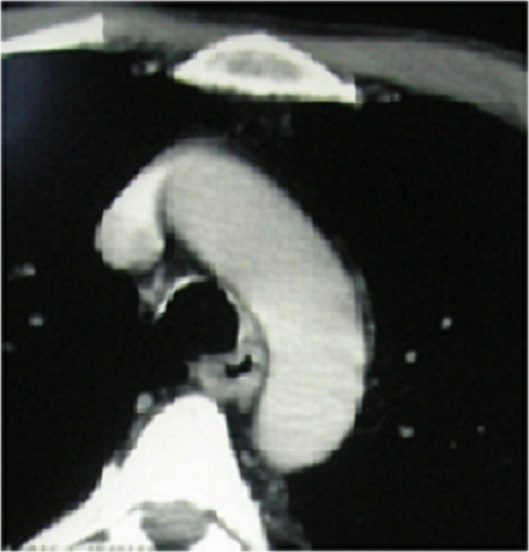

La polychondrite chronique atrophiante est une inflammation des cartilages. C’est une maladie rare, qui se caractérise par des manifestations viscérales polymorphes. Patient âgé de 54 ans hospitalisé pour une douleur et une cyanose du pavillon de l’oreille droite. Il avait une aphtose buccale, une voix rauque, une douleur à la pression du cartilage nasal, une arthrite touchant les interphalangiennes proximales et distales ainsi que des lésions purpuriques infiltrées au niveau de la jambe avec à la biopsie un aspect de vascularite leucocytoclasique. L’examen ORL a trouvé une hypoacousie. Les examens ophtalmologiques et neurologiques étaient normaux. A la biologie, il avait une anémie normochrome normocytaire ( Hb: 11 g/dl) associée à une accélération de la vitesse de sédimentation. Les bilans rénaux et hépatiques étaient sans anomalies. Le bilan immunologique était négatif, ainsi que le bilan de thrombophilie (protéine Cet S et anti-thrombine) éliminant une vascularite ou une connectivite. La TDM laryngo-trachéale a objectivé des calcifications tragiennes , des anneaux trachéaux et de la partie initiale des bronches souches. La biopsie du pavillon a confirmé des lésions de chondrite et périchondrite. La ponction sternale et la biopsie ostéo-médullaire ont permis d’éliminer une hémopathie ou une myélodysplasie. Le diagnostic d’une polychondrite atrophiante compliquée d’une vascularite cutanée a été retenu. Le malade a été traité par corticothérapie (3 boli de solumédrol et relais par prednisone 1mg/kg/j) avec diminution progressive des doses. L’évolution était marquée par la reprise d’un aspect normal du pavillon et la disparition des anomalies cliniques et biologiques.